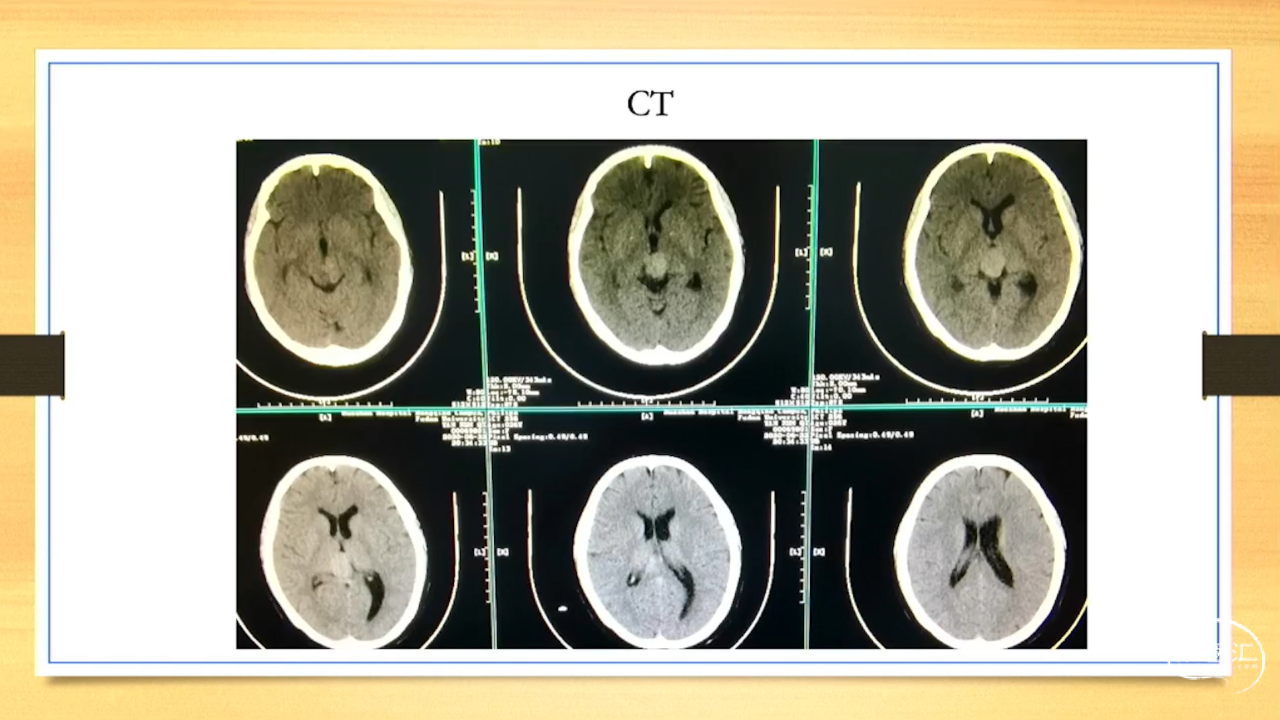

张荣教授:儿童颅内生殖细胞瘤的手术治疗

颅内生殖细胞肿瘤的治疗是手术、放疗、化疗、内分泌及其他多学科的整合治疗。及时、精准、合理的手术治疗是iGCT患者提高生存率、降低并发症、改善神经内分泌功能的关键。